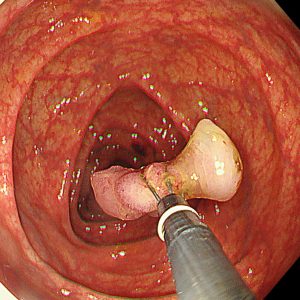

便潜血陽性を認め、人生初めての大腸カメラ検査目的で来院された方です。横行結腸に15mm大の細長いⅠp病変を認めました。拡大NBI観察では一部JNET2A、内視鏡的一括切除を行いました。回収した病変の病理結果は治癒切除でした。上記病変を含めて合計4病変、大腸内視鏡的治療をすることができました。

70歳代 男性 便潜血陽性 #.横行結腸腺腫 15mmⅠp #.多発性大腸腺腫

左:遠景NBI観察、 中:クリッピング術後、 右:病変回収時